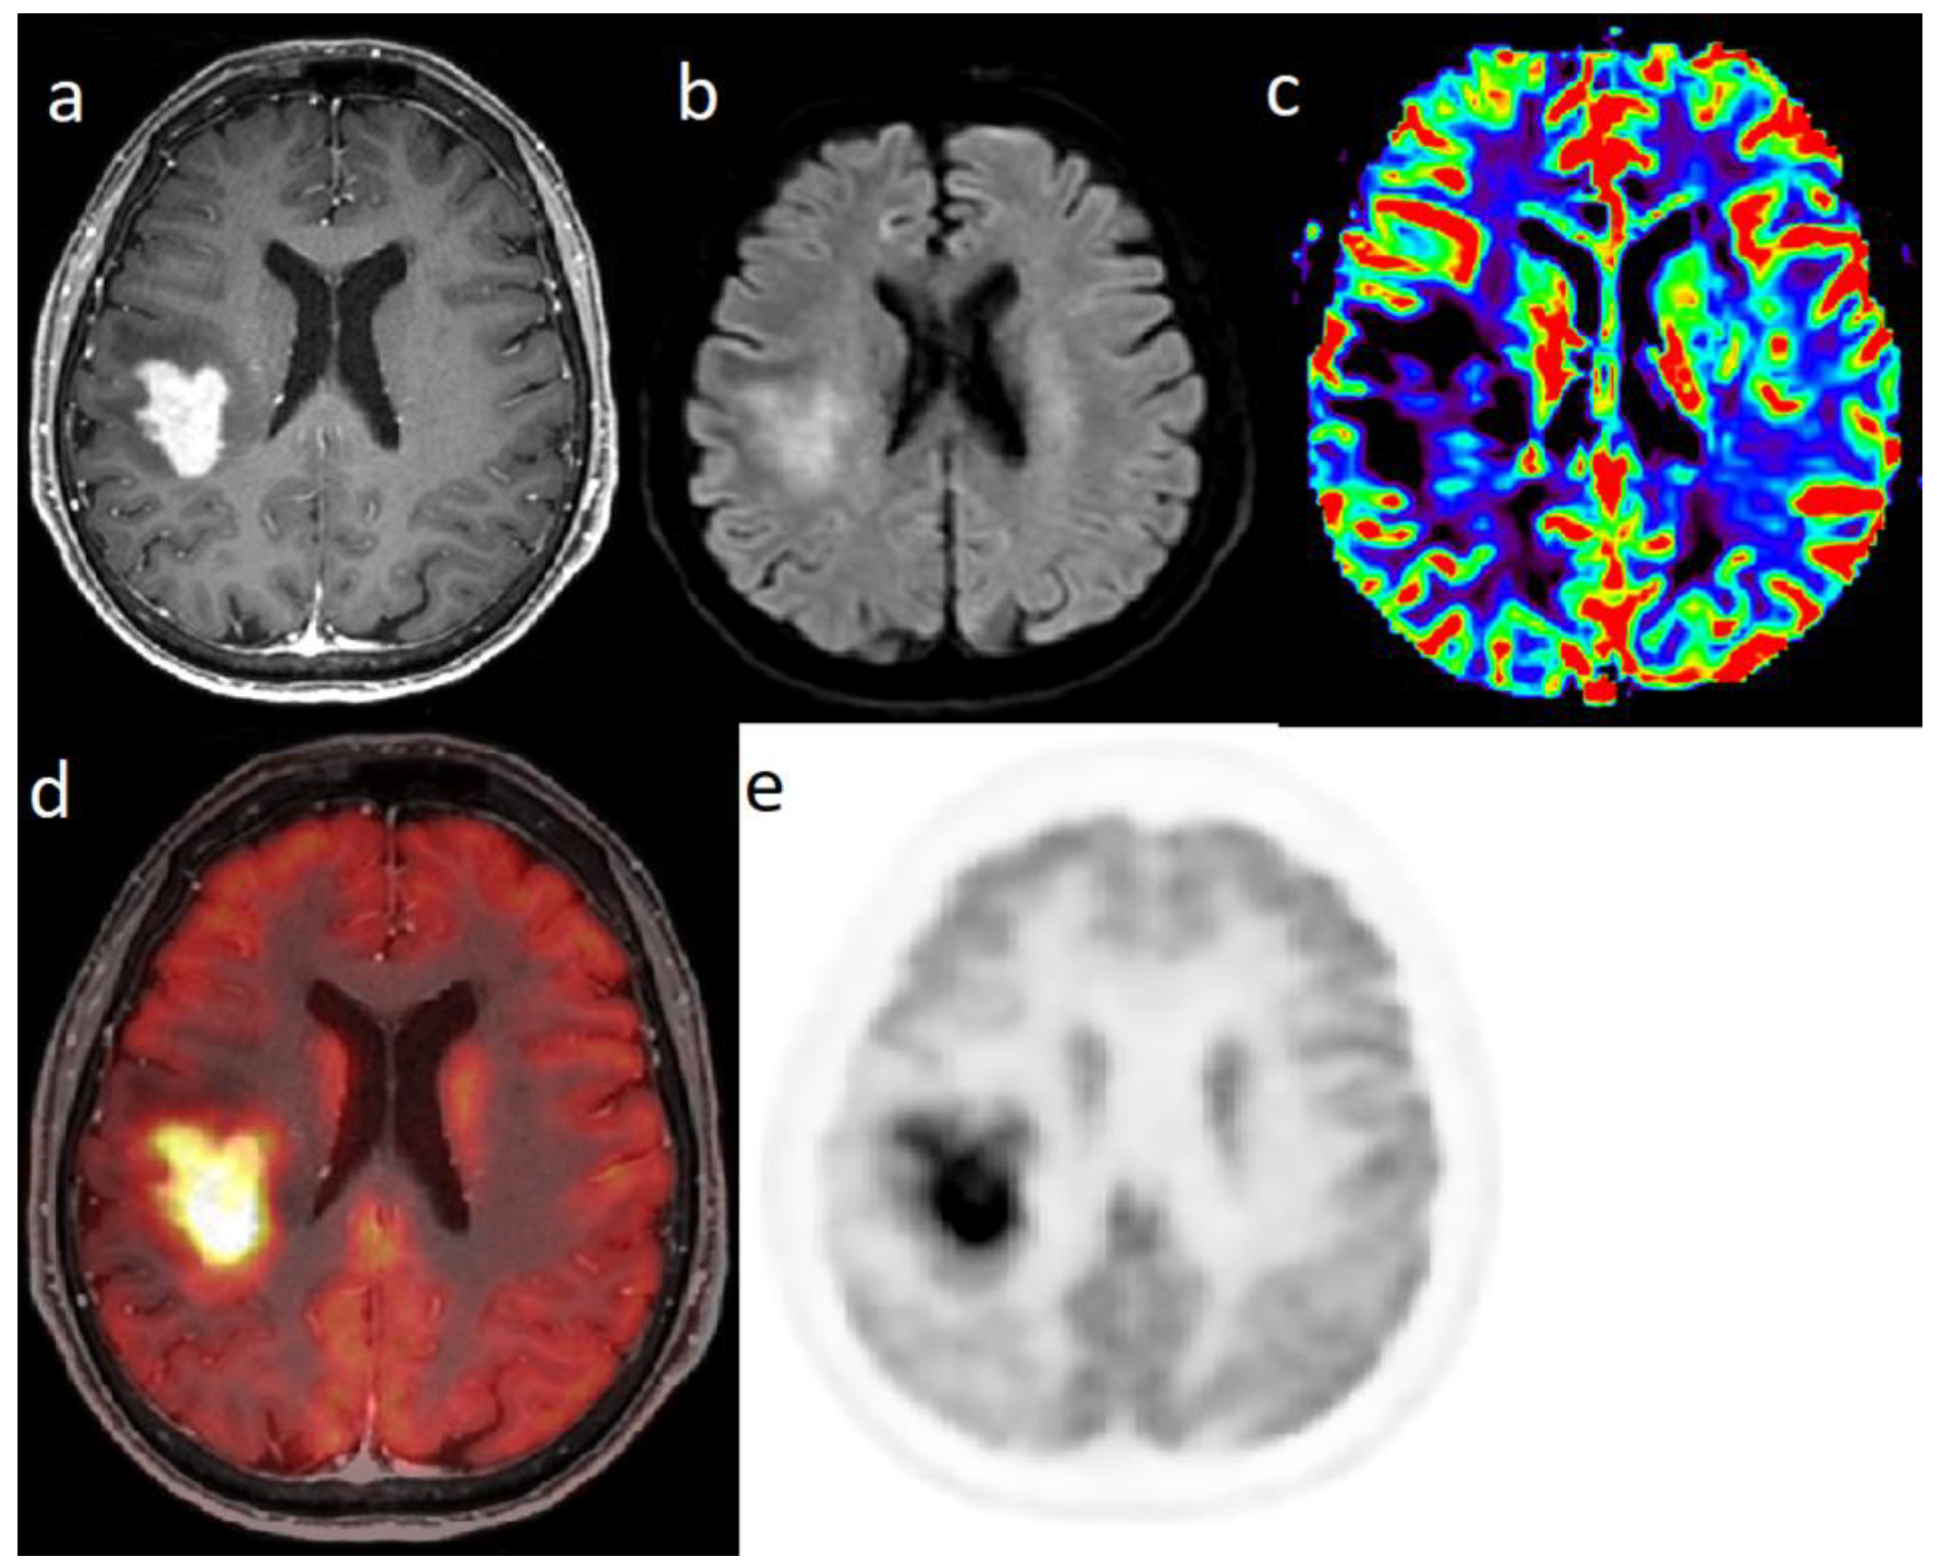

6. PCNSL

- Yang, M.; Sun, J.; Bai, H.; Tao, Y.; Tang, X.; States, L.; Zhang, Z.; Zhou, J.; Farwell, M.; Zhang, P.; et al. Diagnostic accuracy of SPECT, PET, and MRS for primary central nervous system lymphoma in HIV patients: A systematic review and meta-analysis. Medicine 2017, 96, e6676. [Google Scholar] [CrossRef] [PubMed]

- Hatakeyama, J.; Ono, T.; Takahashi, M.; Oda, M.; Shimizu, H. Differentiating between Primary Central Nervous System Lymphoma and Glioblastoma: The Diagnostic Value of Combining 18F-fluorodeoxyglucose Positron Emission Tomography with Arterial Spin Labeling. Neurol. Med. Chir. 2021, 61, 367–375. [Google Scholar] [CrossRef] [PubMed]